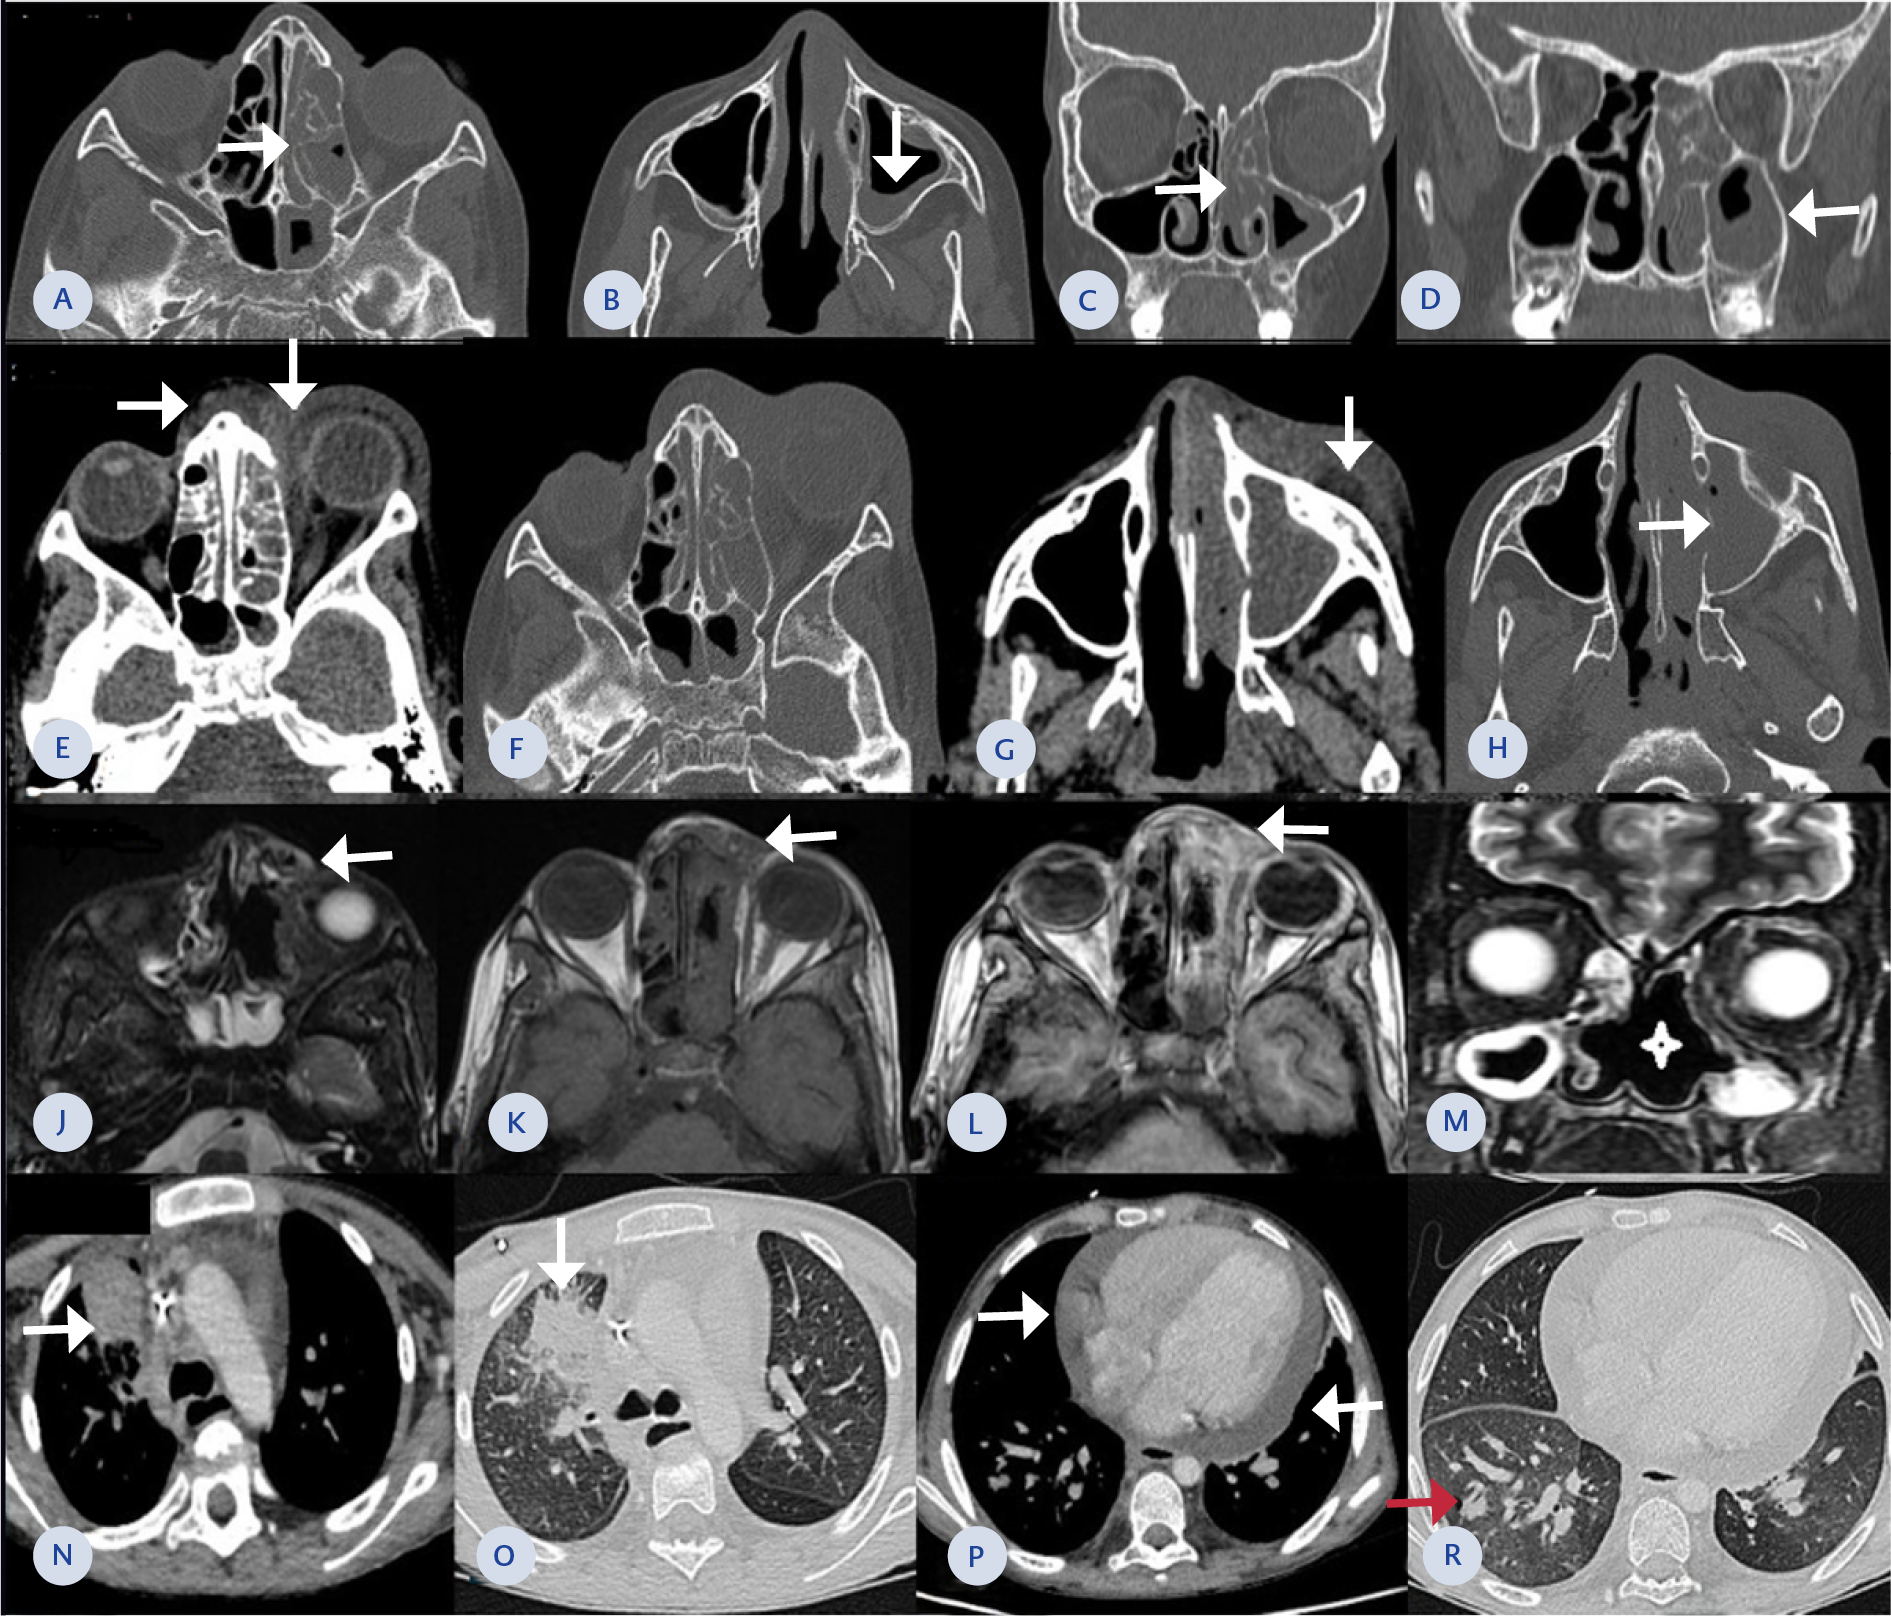

Figure 1. (A-D) Paranasal sinus CT images show loss of ventilation and soft tissue density material in the left ethmoid cells and sphenoid sinus. An air-fluid level is observed in the left maxillary sinus (arrows), accompanied by mucosal thickening. These findings are consistent with chronic sinusitis. No signs of fungal infection, such as high-density material or bone destruction, were present.

(E-H) Orbital CT images reveal soft tissue thickening in the left eyelid and periorbital area. The inflammation extends into the orbital cavity through the postseptal space in the medial orbit (arrows; E), resulting in a proptotic appearance of the left eye. Inflammation also extends toward the nasal root (arrows; A). A limited subcutaneous collection, suggesting an abscess, is noted in the right maxillary area (arrow; G). The right maxillary sinus is filled with soft tissue density, and thinning of its medial wall is observed (arrows; H).

(J-M) Facial MRI shows regression of inflammation in the left ethmoid sinuses. However, subcutaneous inflammation persists on the nasal side of the left periorbital region (arrows; J, K, L). Inflammation in the left orbit has decreased. Destruction is noted in the nasal septum and middle turbinates (asterisk; M). Mucosal thickening persists in the maxillary sinuses.

(N-R) Thorax CT images show improved homogeneity of parenchymal aeration. An irregular consolidation adjacent to the mediastinum is seen in the anterior segment of the right upper lobe, with surrounding ground-glass opacity (arrows; N, O). Pericardial effusion is present (arrows; P). A peripheral, peribronchial nodular lesion is observed in the posterobasal region of the right lower lobe (red arrow; R).

During follow-up, swelling and erythema around the left eye worsened, accompanied by persistent fever. Paranasal CT demonstrated reduced air content and significant thinning of the bone structures, with peripheral mucosal thickening observed in both maxillary sinuses, anterior and posterior ethmoidal cells, and other sinus compartments (Figure 1. A-D). Orbital CT was consistent with preseptal cellulitis. Nasal endoscopy revealed minimal dryness, and a biopsy was taken from the affected area. Preliminary pathology showed necrotic fungal structures, including both septate and non-septate forms, primarily suggesting mucormycosis. However, the sample could not be definitively interpreted due to ongoing antifungal treatment.

Despite these interventions, the absolute neutrophil count (ANC) remained <100 cells/mm³, and repeated granulocyte transfusions failed to increase it. Ocular symptoms continued to worsen. Orbital CT revealed progression from left preseptal cellulitis to orbital cellulitis, with worsening sinusitis findings. Inflammation had extended into the orbital cavity, involving the postseptal region (Figure 1.E-H). Exenteration surgery was discussed with the family, but they declined the procedure despite vision loss. A revision FESS was performed, including cavity debridement, left orbital decompression, abscess drainage, and left medial maxillectomy. The L-AmB dose was increased to 10 mg/kg/day.

Although the patient initially remained clinically stable, facial swelling and fever recurred on day 49 of antifungal therapy. Magnetic resonance imaging of the face revealed a hypodense, spherical, lobulated abscess (17×12×10 mm) in the left orbital medial area near the nasal root, consistent with abscess formation. The abscess was drained, and fungal cultures returned negative. At the three-month follow-up, inflammation in the left ethmoid sinuses and left orbital space had regressed (Figure 1. J-M). With radiological and clinical improvement, caspofungin was discontinued on day 75.

However, on day 137, the patient developed tachypnea and oxygen desaturation. Chest CT revealed a nodular lesion (8×10 mm) adjacent to a vascular structure in the right lower lung lobe, consistent with Aspergillus infection (Figure 1. N-R). Breakthrough IA was diagnosed, and the treatment regimen was adjusted to L-AmB (10 mg/kg/day), caspofungin (70 mg/day), and isavuconazole (200 mg/day, oral). Despite these measures, the patient, who had a severe neutropenia and hypogammaglobulinemia, passed away on day 151 of antifungal treatment. The antifungal combination therapy used in this patient is summarized in Table 1.